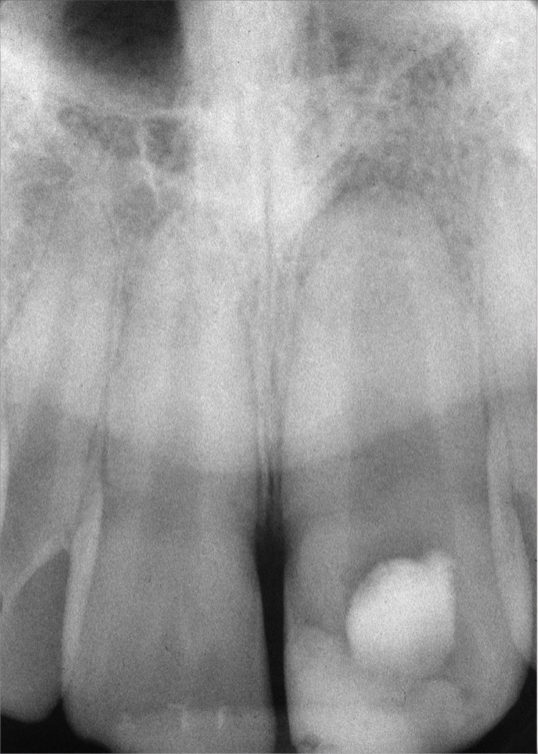

Clinical procedure: Regeneration of the endodontic pulp space is indicated for cases with very thin dentinal walls and an open apex that is more than 1 mm in diameter radiographically (Figure 4). Disinfection of the root canal system is performed using sodium hypochlorite irrigation followed by a triple antibiotic paste dressing that is left in place for 1 week. At the second visit, ethylenediaminetetraacetic acid (EDTA) is used to condition the dentin walls, which results in the release of growth factors, and bleeding is stimulated in the periapical tissues (where stem cells are located), with the aim of filling the pulp space with a stable blood clot, which would serve as the scaffold. MTA is then placed at the canal orifice in contact with the clot to protect it from coronal microleakage (Figure 5 and Figure 6). In time, the clot should be replaced with a reparative tissue of variable composition, and the root walls should continue to thicken due to the deposition of a dentin-like material on the pre-existing root dentin27,28 (Figure 7 and Figure 8).

Fig 7. 1-year follow-up showing a healthy lamina dura and root development.

Figure 7

Fig 8. 3-year follow-up showing continued root development.

Figure 8